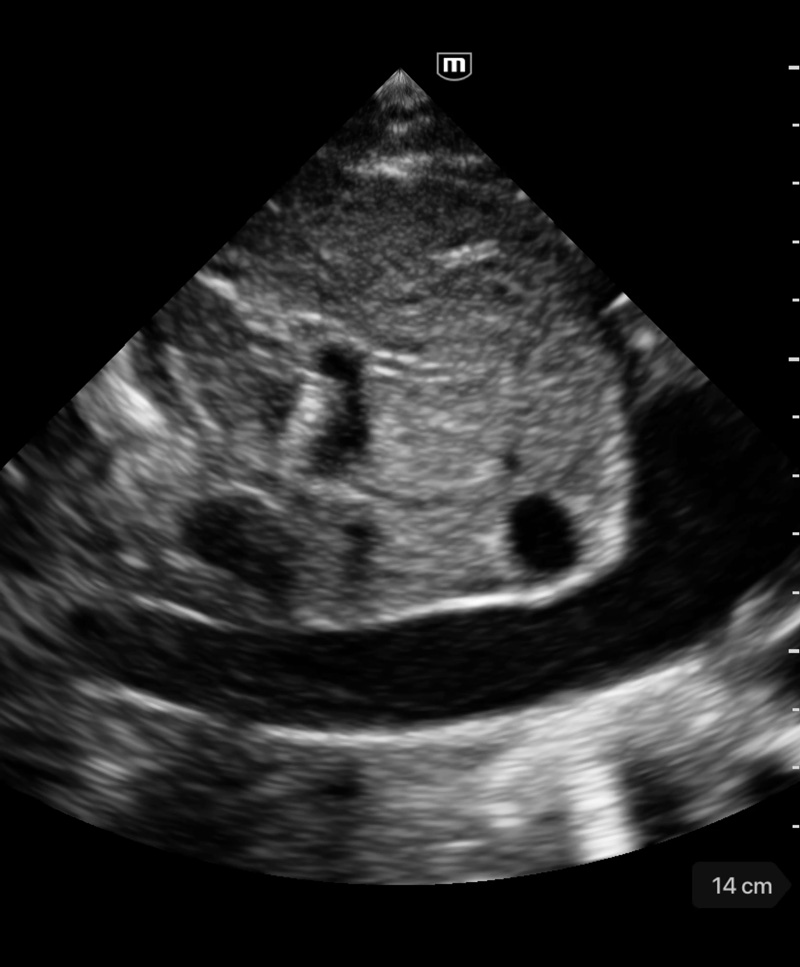

Професионално качество на диагностичните изображения

Предварително зададени приложения

Различни режими на изображението

Множество режими за сканиране

B mode

Клинични снимки